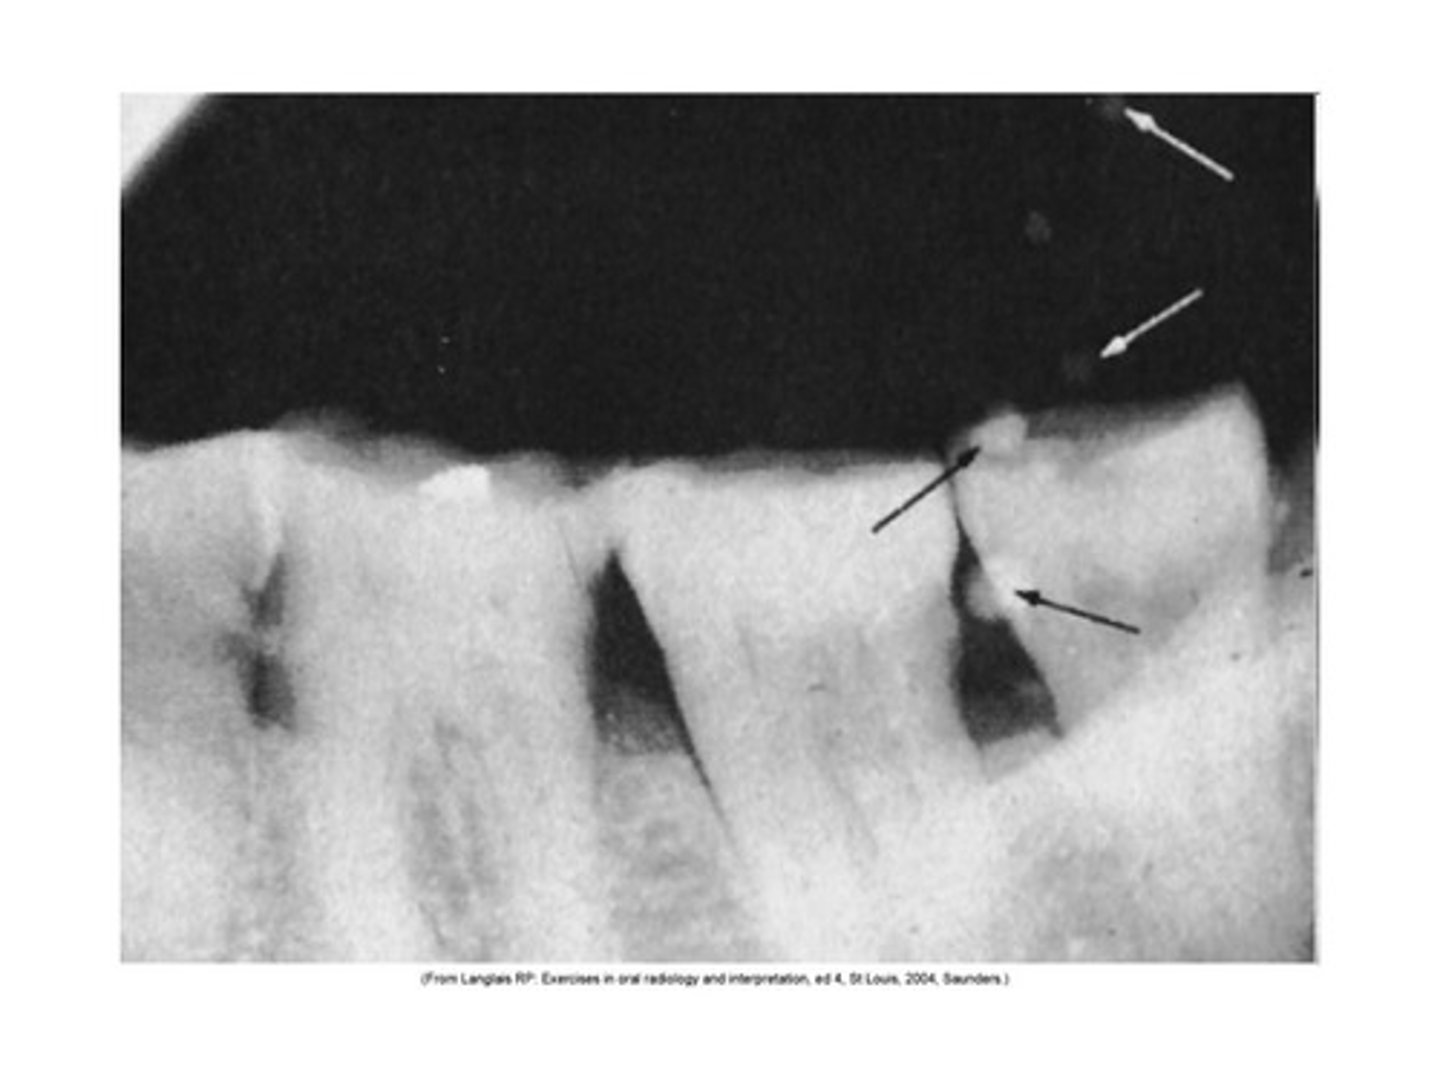

Developer cutoff

straight white border caused by undeveloped part of film from low level of developer

<p>straight white border caused by undeveloped part of film from low level of developer</p>

fixer cutoff

Straight black border

Unfixed part of film from low level of fixer

<p>Straight black border</p><p>Unfixed part of film from low level of fixer</p>